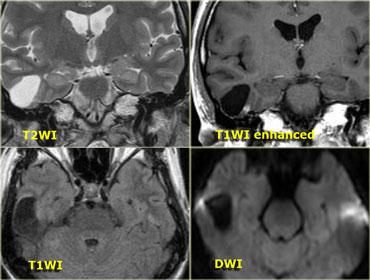

Hình bên trái là bệnh nhân nam 52 tuổi với biểu hiện nghe kém bên phải.

Hình ảnh cho thấy một khối nang bất thường với các vách ngăn ngấm thuốc.

Ngoài ra còn có ngấm thuốc trong ống tai trong.

Dựa trên hình ảnh, chẩn đoán có khả năng nhất là u bao thần kinh dạng nang (cystic schwannoma), tuy nhiên đây thực ra là một trường hợp hiếm gặp, biểu hiện dạng nang của u màng não (meningioma).